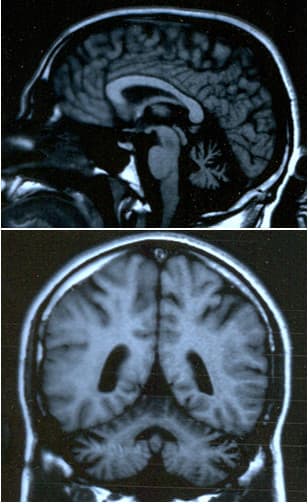

En médecine, l'ataxie (du grec ataxiā, signifiant « désordre ») ou danse des tendons est une maladie neuromusculaire qui consiste en un manque de coordination fine des mouvements volontaires. Elle est liée à une atteinte du système nerveux. Le trouble de la coordination est partiellement corrigé par le contrôle visuel. Le cervelet est le centre de la coordination fine des mouvements des muscles, tandis que l'information qui en émerge est véhiculée jusqu'aux muscles par la moelle épinière et les nerfs périphériques. Pour cette raison, un trouble soit dans la moelle épinière soit dans les nerfs périphériques peut causer une ataxie. L'ataxie se manifeste principalement par des troubles de la marche, de l'équilibre postural et de la station debout, du guidage des mouvements par la vue ou le toucher (marche dans le noir par exemple). Elle s'observe par le phénomène de rebond, il n'y a pas de frein dans le mouvement, le sujet dépasse la cible en raison d'un freinage tardif des muscles antagonistes. Les ataxies font partie d'un ensemble plus grand : les troubles de l'équilibre. Les troubles de l'équilibre sont plus évidents quand le patient a les yeux fermés dans le cas d'une ataxie labyrinthique. Il est donc important de se renseigner sur ce type de troubles avant d'effectuer le bilan psychomoteur. En effet, certaines épreuves sont à éviter. Dans l'ataxie labyrinthique (atteinte au niveau du système labyrinthique), on pourra observer des troubles de l'équilibre et une déviation à la marche. Dans l'ataxie cérébelleuse (atteinte au niveau du cervelet), l'exécution de mouvements volontaires va être perturbée dans certaines directions. De plus, on observera une asynergie et des dyschronométries. Dans l'ataxie par déficit de sensibilité profonde, il y a des troubles de l'équilibre en statique, à la marche, et lors de la coordination segmentaire des membres. Syndrome de Joubert Ataxie cérébelleuse AVED ataxie avec déficit isolé en vitamine E Ataxie de Friedreich : maladie génétique chronique à transmission autosomique récessive.